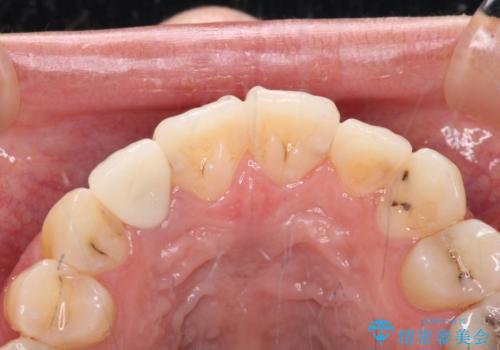

以前治療した前歯をきれいに治したい オールセラミッククラウン

- 根管治療はやり直さずに、ファイバーポストを使用した土台を植立して、オールセラミッククラウンにて補綴することとしました。

神経を取り除いた歯の変色は、クリーニングやホワイトニングでは改善できないため、オールセラミッククラウンなどによる補綴治療が必要となります。